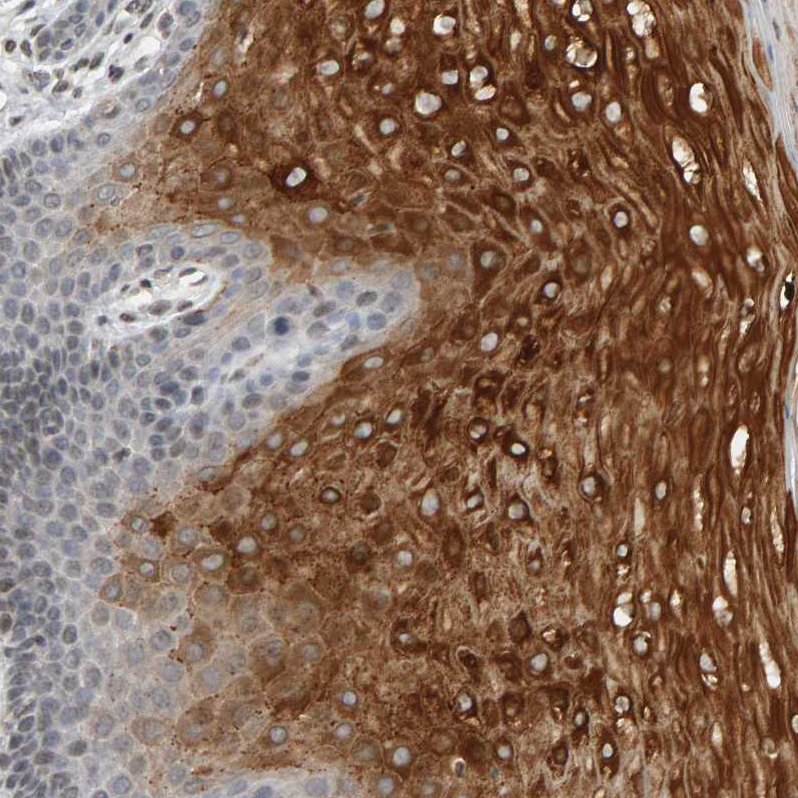

Immunohistochemical staining of human liver shows strong granular cytoplasmic positivity in hepatocytes.